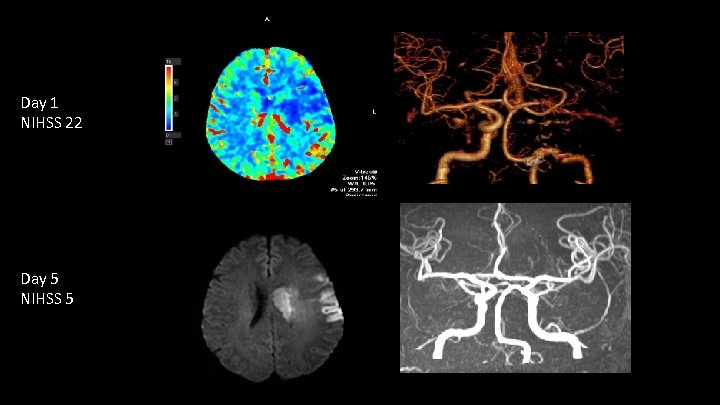

Multimodal Imaging UCI Stroke Center

Follow up Substantial improvement within 24 hours: Patient is moving the right side against gravity, comprehends and utters simple words = NIHSS 10 UCI Stroke Center

Day 1 NIHSS 22 Day 5 NIHSS 5 UCI Stroke Center